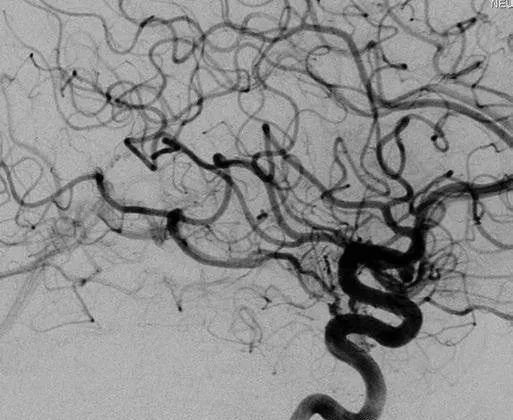

但3年后造影显示:颞叶内侧仍残留少量畸形团,并向基底静脉环(BVR)引流——这意味着畸形血管仍存在破裂风险。

颞叶内侧少量残留畸形团向BVR引流(右ICA造影,侧位)